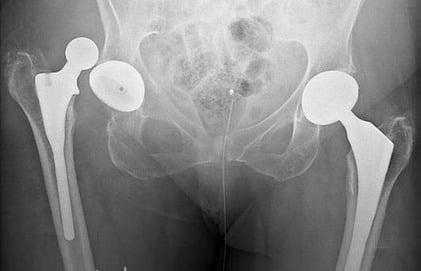

Рентгенограмма после операции по поводу травмы таза, тазобедренного сустава, бедра

Изображение положения эндопротеза в теле человека.